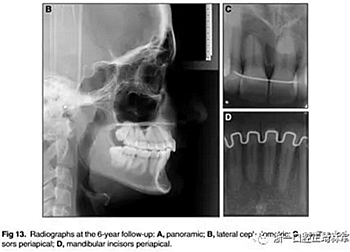

6年后治療結(jié)果保持穩(wěn)定(圖11,圖12 ; 圖13)??梢杂^察到穩(wěn)定的間隙關(guān)閉,正常的覆蓋和覆合,上下牙中線一致,微笑美觀。建議完美替代了拔除的側(cè)切牙。正畸治療后進行牙齒美白。

頭顱測量疊加(圖14)顯示,面部特征在治療過程中發(fā)生變化,并在6年的隨訪評估中保持穩(wěn)定。上頜骨和下頜骨的區(qū)域疊加也表明治療期間的單純牙齒移動和骨骼穩(wěn)定性。在后續(xù)檢查中獲得并維持適當?shù)母采w和覆蓋(表格)。